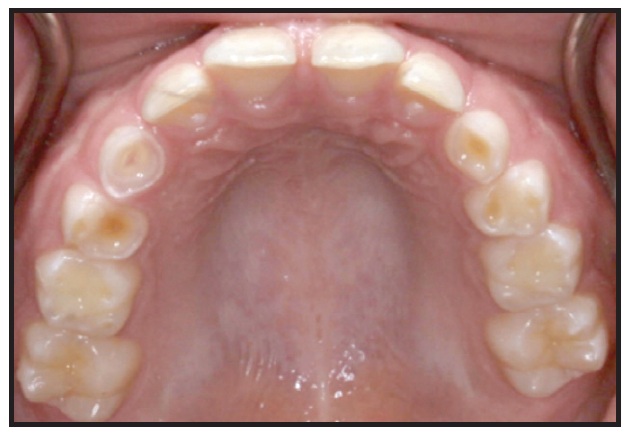

8. GERD: A known side effect of OSA,17 GERD presents as smooth, mother-of-pearl-like depressions on the occlusal or lingual surfaces of the teeth (Fig. 1).

Fig. 1 8-year-old male showing dental depressions characteristic of gastroesophageal reflux disease.